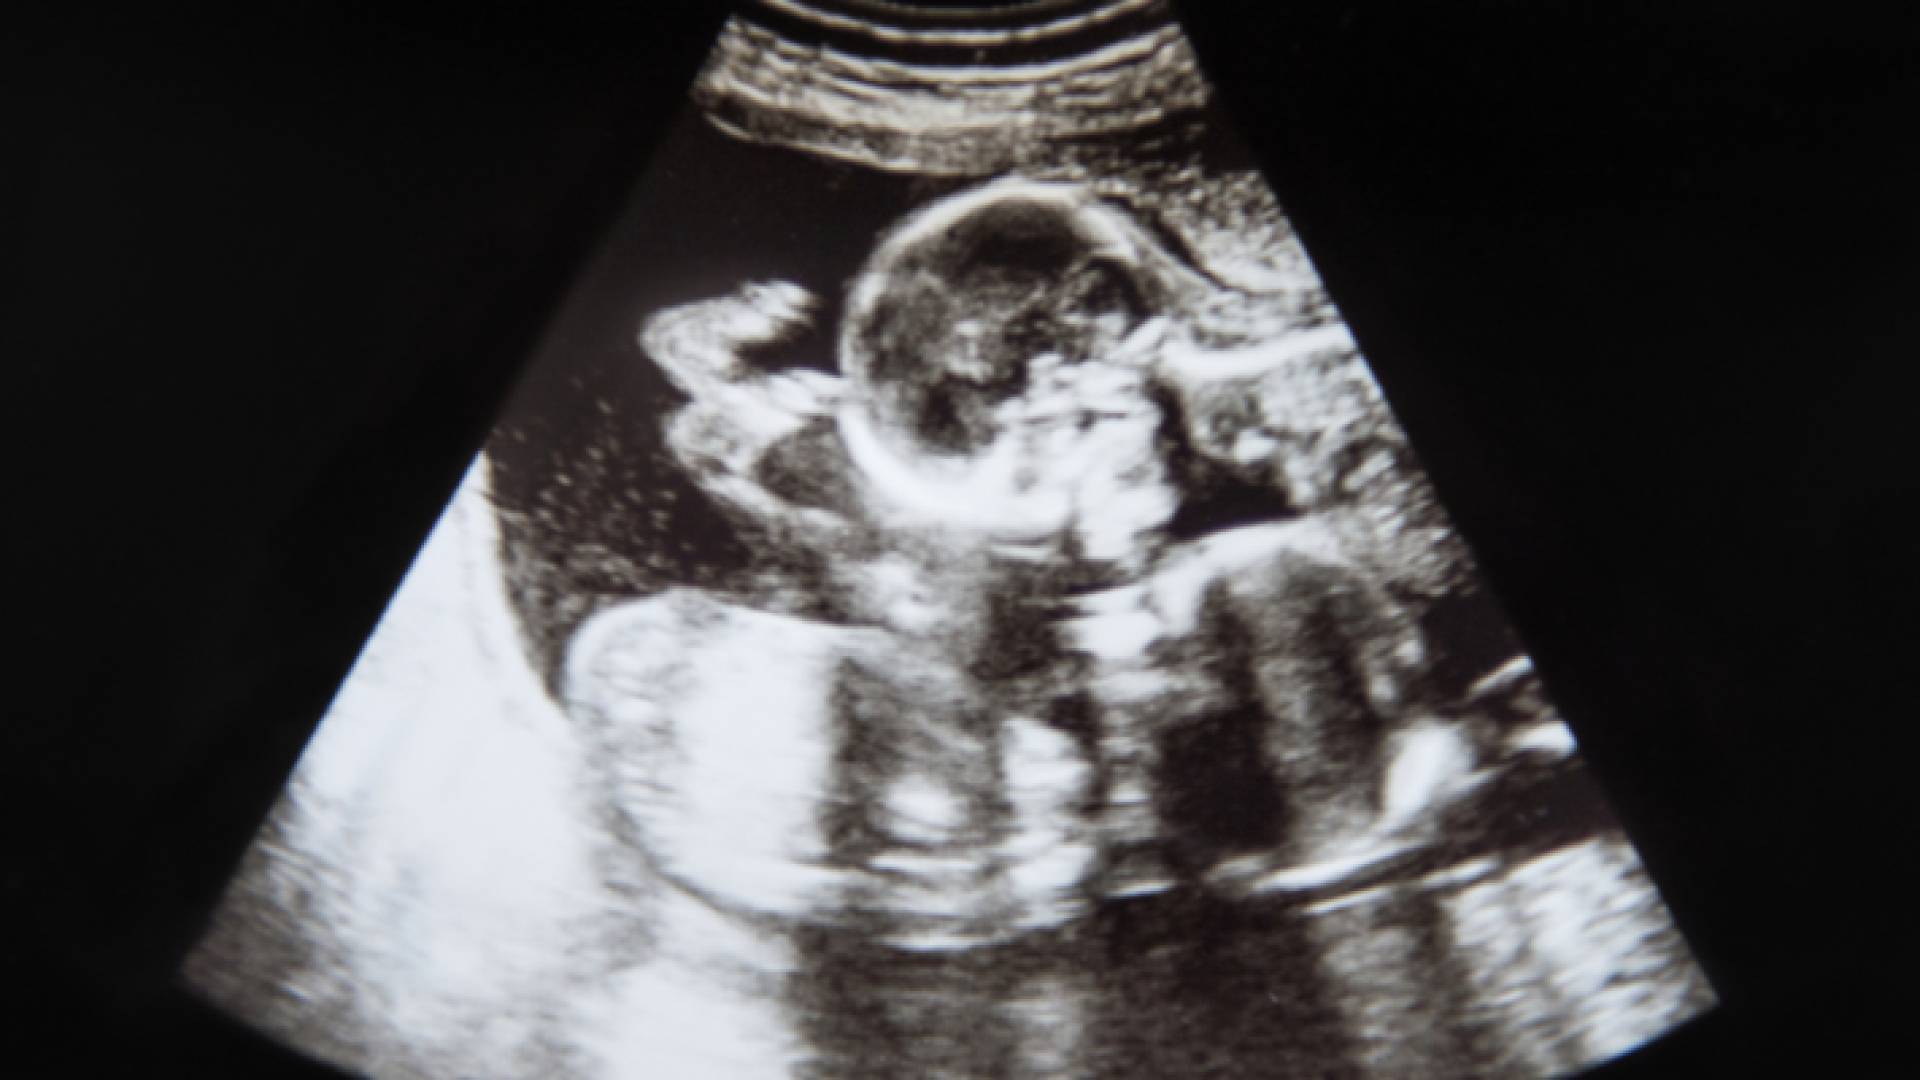

صورة من الفيديو

فيديو لشجار وملاكمات متبادلة بين توأمين داخل رحم أمهما.. شاهد

كشف مقطع فيديو تم التقاطه لشجار وملاكمات متبادلة بين توأمين داخل رحم أمهما، في الصين.

وبحسب ما نقلت صحيفة Metro البريطانية، فان الجنينين كانا يتعاركان في رحم والدتهما كما لو أنهما في جولة ملاكمة، إذ يحاول أحدهما دفع الآخر، ثم يتبادلان الأدوار.

الفيديو التقط عبر الموجات فوق الصوتية بينما كانت الأم في شهرها الرابع. قال أبوهما تاو، البالغ من العمر 28 عاما، إنه صورهما عندما ذهب مع زوجته لإجراء فحص ما قبل الولادة في مدينة ينشوان، وفقا لما نشرته .